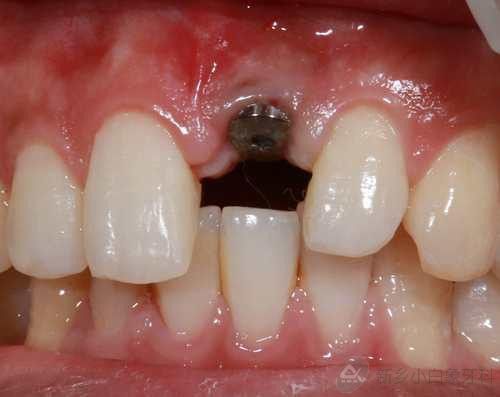

2.jpg

治疗中